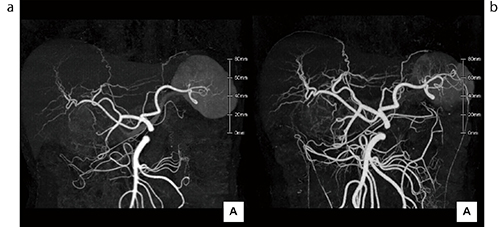

図1 化学療法前後の同一症例

a:化学療法前:通常のCTA、b:化学療法後:ニトログリセリンを使用したCTA

ニトログリセリンを用いることによって、通常のCTAでは描出できていなかった

腹部末梢血管の描出能が向上している。